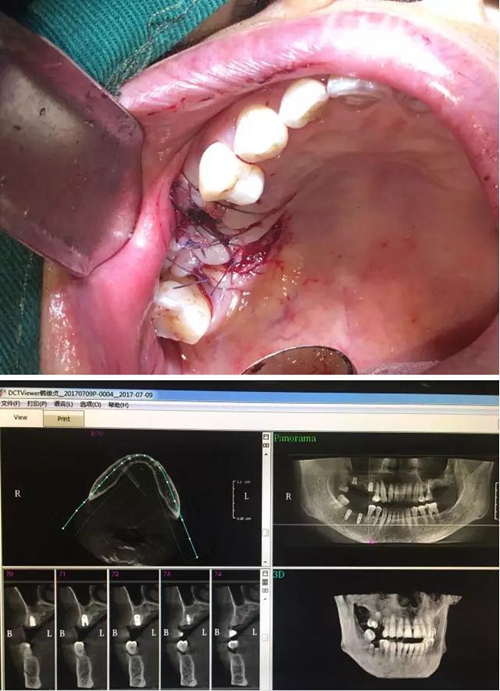

【病例分享】內(nèi)提,用自體骨柱,不用骨粉

2.jpg

3.jpg